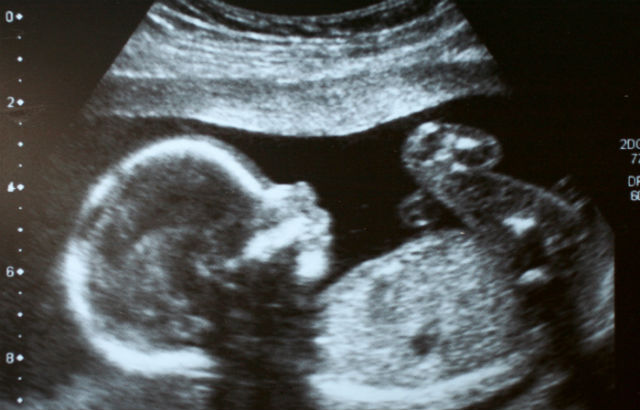

The claimant, Justyna, is a Polish national who came to London in 2004. She married a British man in 2007 and they moved to Lincolnshire. In 2012, she became pregnant. The couple were overjoyed and prepared for the birth of their daughter, Megan. However, all did not go well and in May 2013, labour was induced, ten days after the due date. It transpired that Megan had died in utero but an eighteen-hour labour had to proceed for Justyna to give birth to the couple’s stillborn daughter. She was discharged from hospital on 28 May 2013, the day after the birth.